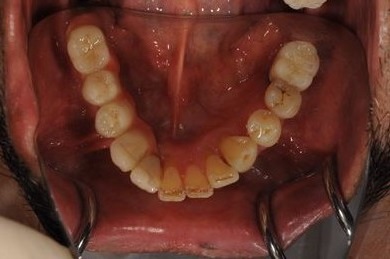

骨再生スピードインプラント治療+遊離歯肉移植

| 治療内容 | インプラント8本(サイナスリフト、抜歯即日スピードインプラント)、ハイブリッドセラミッククラウン9本、遊離歯肉移植 | ||||||||||||||||||||||||||||||||

| 治療期間 | 1年0ヶ月 |